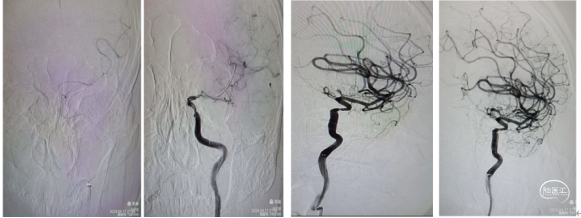

3、裸支架导丝技术:缓慢撤出微导管于体外,裸支架导丝,保留中间导管最大管腔。

4、中间导管收拢支架尾部一体回撤:中间导管跟进至M1段收拢支架尾部下,负压踹马桶抽吸中间导管,缓慢一体回撤支架和中间导管,一次取出长约3.5cm黯红色血栓。

5、二次抽吸清理:迅速清理导管进行二次抽吸未抽吸出肉眼血栓。

造影显示:

大脑中动脉畅通,远端血流达3级。但分叉以远分支似有少量血栓。考虑6x30m支架放置M2段过大,未再进行远端分支取栓,经导引导管给予替罗非班6ml推注。结束手术。